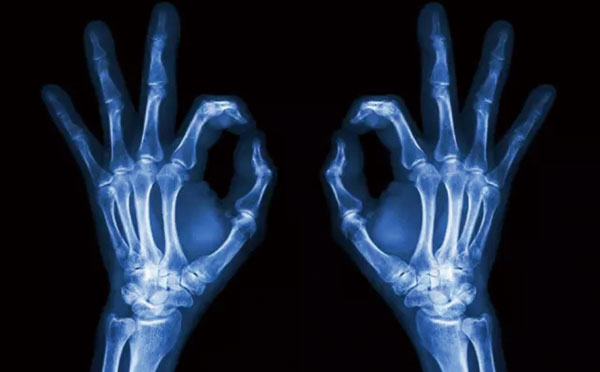

X线像把面包压扁了看

X线会穿过人体,遇到被遮挡的部位,底片上不会曝光,洗片后这个部位就是白色的。

就像一片面包或一块棉花,看不到里面的纤维纹理,但用手压瘪了会清晰一些。X线最大缺点是受制于深浅组织的影像相互重叠和隐藏,有时需要多次多角度拍摄X线片。

1、外伤骨头——粗看X线片,细看CT,核磁看不清

各种外伤,如果怀疑伤到了骨头,优先选择X光照片,检查结果快速易得。若要进一步观察,可以选择CT。超声、核磁对于骨皮髓质等看不大清,一般不选择。